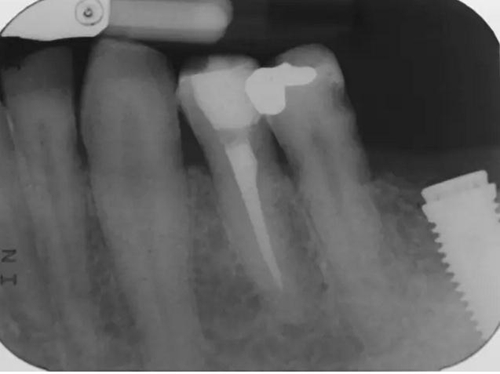

圖4 該病例中,左下4根充失敗,左下5牙髓壞死。兩個牙齒均需要根管治療和修復。

圖5 根管治療術后。左下4需要使用纖維樁,并用雙固化樹脂粘結劑粘結。左下5無需纖維樁。但2個牙齒均需要進行覆蓋牙尖的修復。

圖7 術后片。左下4重新疏通。根尖4mm牙膠封閉,根管內粘結了纖維樁。左下5根尖有根分叉。在根管冠段,可以樹脂(SDR)進入,輔助固位。